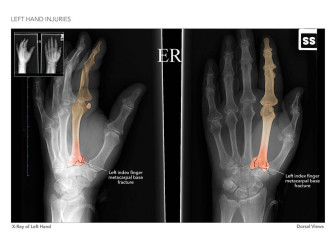

Available in high resolution JPEG or PDF formats, 8x10 print, or laminated foam core exhibit board (24x46, 30x40 or 36x48).